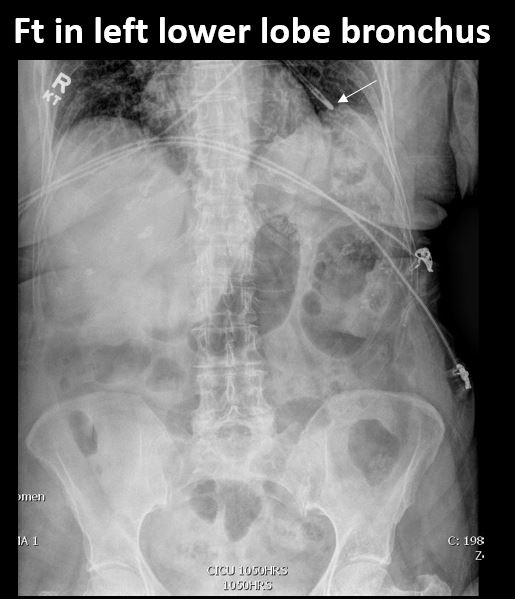

There is a FT in place and the tip of the FT is properly located at the ligament of Trietz, and is NOT otherwise malpositioned. |

Yes | NA |